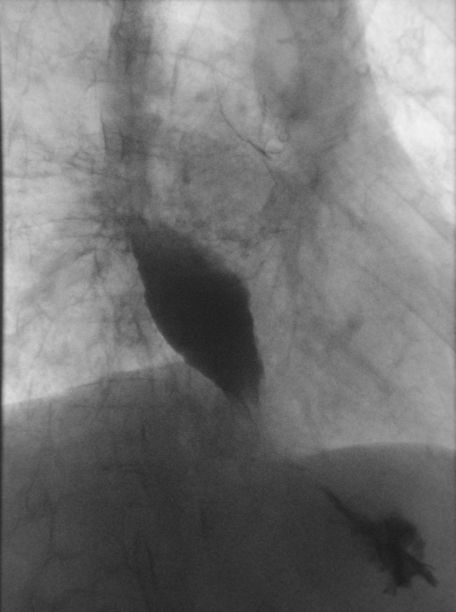

Therapie - Folgen 82jähriger, wettergegerbter Schmied, der sich ausschließlich von passierter Kost ernährte. Vor einem Jahr Bestrahlung des Tumors und des mediastinalen Lymphabflussgebietes mit 50 Gy, ED 2 Gy , Tumorboost bis 60 Gy. Jetzt: Erheblich dilatierter Ösophagus bei hochgradig filiformer Stenose von ca. 5 cm Länge im distalen Ösophagusabschnitt (Übergang in den Magen) mit Kontrastübertritt in den Magen. Bei normaler Schluckmenge Nachweis einer massiven Aspiration (Bronchien enthalten Kontrastmittel!). Eine proximale ösophagotracheale Fistel ist nicht sicher nachweisbar.